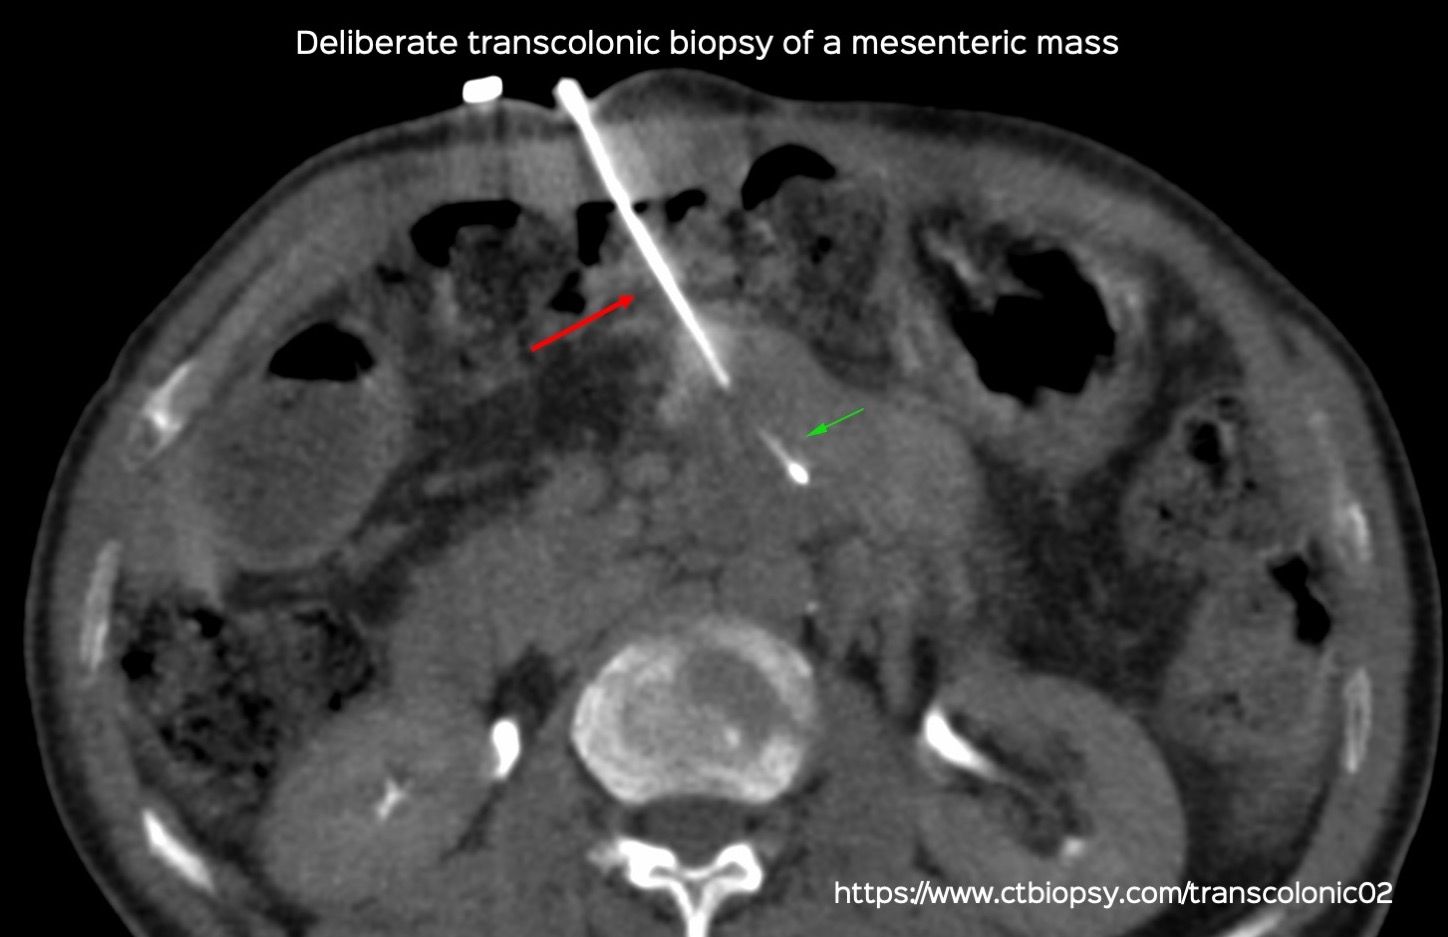

Case 80: Deliberate Transcolonic Biopsy of a Mesenteric Mass

Bhavin Jankharia - 19 February 2022